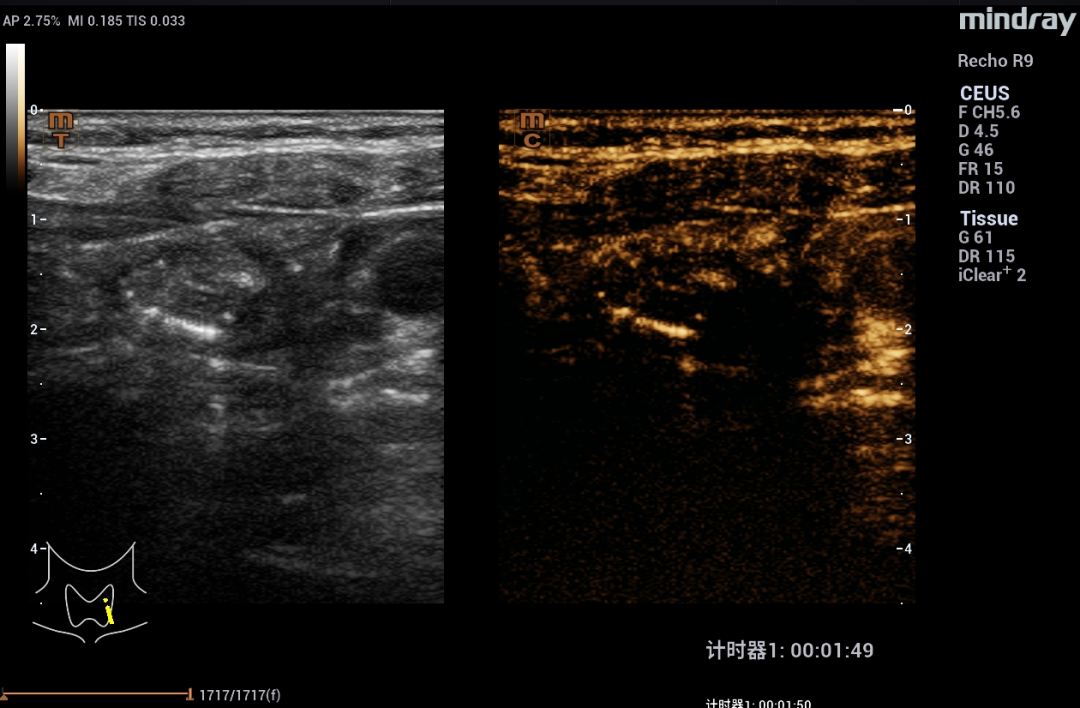

在静脉注射少量造影剂后,发现这个“团块”边缘有反应,但里面空空如也,几乎没有血流信号——这提示它不是实心的肿瘤。

血池造影